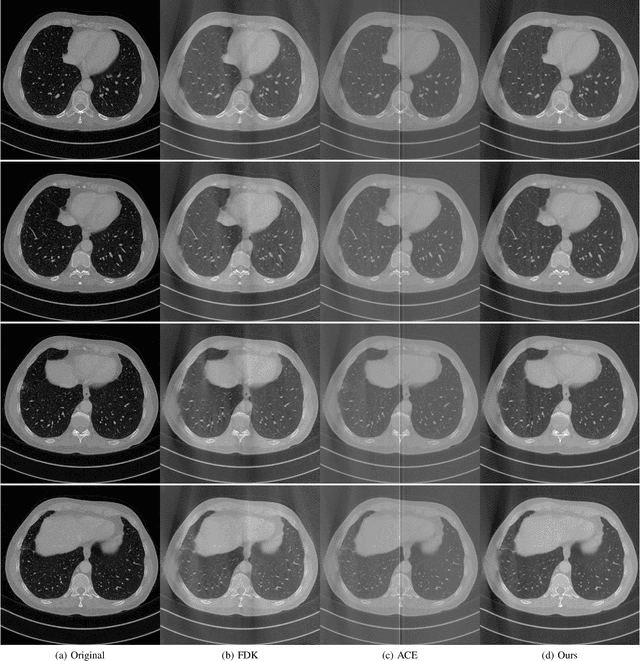

Abstract:In this paper, we propose a new GPU implementation of the Katsevich algorithm for helical CT reconstruction. Our implementation divides the sinograms and reconstructs the CT images pitch by pitch. By utilizing the periodic properties of the parameters of the Katsevich algorithm, our method only needs to calculate these parameters once for all the pitches and so has lower GPU-memory burdens and is very suitable for deep learning. By embedding our implementation into the network, we propose an end-to-end deep network for the high pitch helical CT reconstruction with sparse detectors. Since our network utilizes the features extracted from both sinograms and CT images, it can simultaneously reduce the streak artifacts caused by the sparsity of sinograms and preserve fine details in the CT images. Experiments show that our network outperforms the related methods both in subjective and objective evaluations.